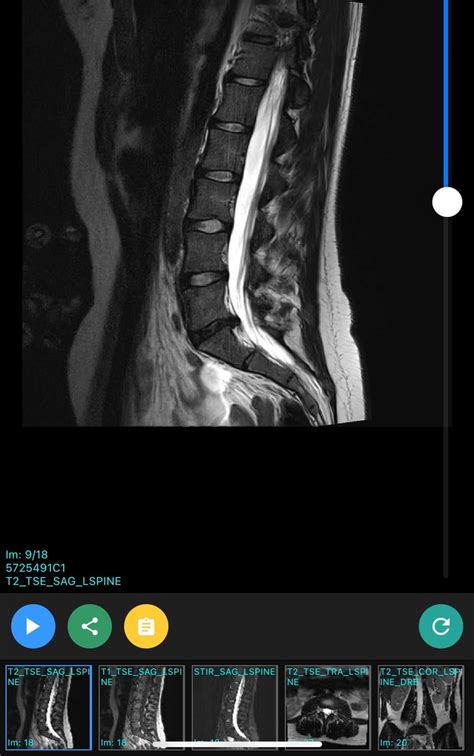

Diagnosing Grade 1 Retrolisthesis

Diagnosing Grade 1 Retrolisthesis typically involves a combination of physical examinations and imaging tests. The diagnostic process may include:

• Imaging Tests: X-rays, CT scans, and MRI scans to visualize the spine and identify any misalignments.

Imaging tests are particularly crucial for diagnosing Grade 1 Retrolisthesis, as they provide a clear view of the vertebrae and any slippage. MRI scans are often preferred for their detailed images of soft tissues, which can help identify nerve compression and other issues.